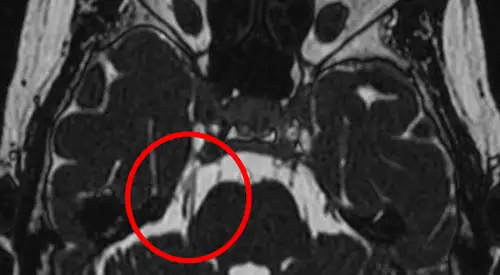

Aunque los estudios de neuroimagen son normales en la mayoría de los casos, la resonancia magnética de alto campo (RM) permite observar bucles vasculares y compresiones de vasos sobre el nervio trigémino que en estudios convencionales de RM suelen pasar desapercibidos, además de descartar tumores, enfermedades desmielinizantes etc.